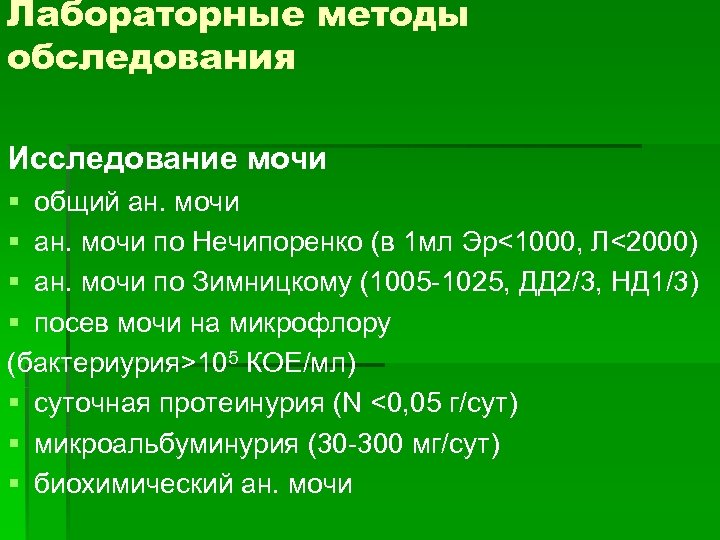

Лабораторные методы обследования Исследование мочи § общий ан. мочи § ан. мочи по Нечипоренко (в 1 мл Эр<1000, Л<2000) § ан. мочи по Зимницкому (1005 -1025, ДД 2/3, НД 1/3) § посев мочи на микрофлору (бактериурия>105 КОЕ/мл) § суточная протеинурия (N <0, 05 г/сут) § микроальбуминурия (30 -300 мг/сут) § биохимический ан. мочи